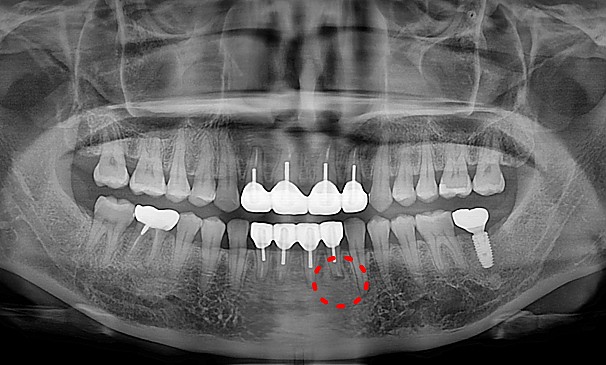

뿌리염증 제거술란?

치아 뿌리 끝에 염증이 생긴 경우는 몇 가지의 원인이 있습니다. 교합문제나 다른 자연 발생적으로 생긴 염증일 수 있고,

이미 신경 치료된 치아가 어떤 이유에서 다시 감염 되었을 때도 뿌리에 염증이 생길 수 있습니다. 염증이 생긴 원인과 염증 범위에 따라 여러 가지 형태로 치료할 수 있습니다.

이OO님 전후사진 | 치료 기간 : 3개월 후

치료 전